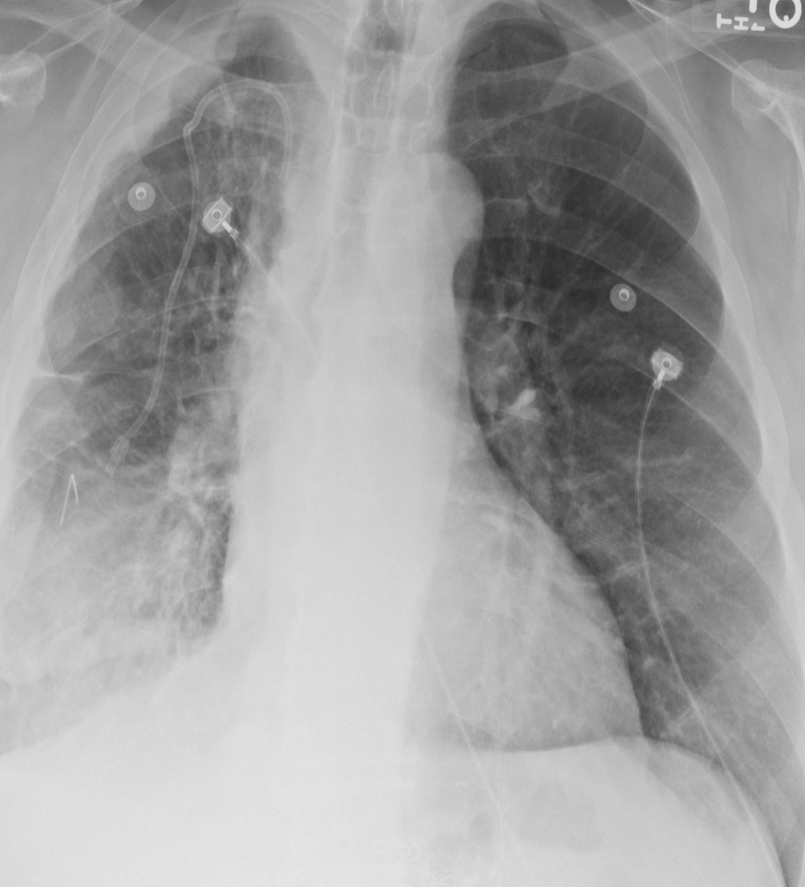

We conduct rigorous quality control to ensure the integrity of our segmentation masks. Masks are retained only if (i) lung pixels occupy between 8% and 90%of the image, and (ii) there are at least two external contours present. Accepted masks define the tightest bounding box around the two largest contours. The corresponding region is cropped from the original CXR to focus subsequent analysis on parenchymal tissue while minimizing background artifacts. Any image failing these automatic checks or showing residual issues during subsequent manual review (such as embedded lead markers) is discarded. This procedure resulted in the elimination of 337 normal, 237 tuberculosis, 1,642 COVID-19, and 2,976 symptom-labelled images, leaving a curated dataset of 1,904 tuberculosis, 3,163 normal, 2,358 COVID-19, and 12,024 symptom CXRs, totalling 19,449 images. Fig. 2 presents sample images from the dataset, showcasing both original and cropped versions, demonstrating how the segmentation and cropping process isolates relevant regions while reducing background noise.